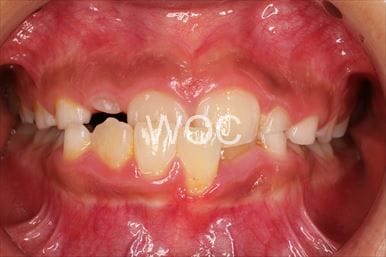

叢生

治療前1

治療前2

治療前3

治療前4

治療前5

- 年齢:7歳9ヶ月

- 主訴:スペースがない、デコボコしている

- 診断名:叢生、上顎前突、過蓋咬合

- 装置:可撤式拡大装置、機能的矯正装置

- 期間:4年1ヶ月 ※

- 費用:基本矯正料金:380,000円